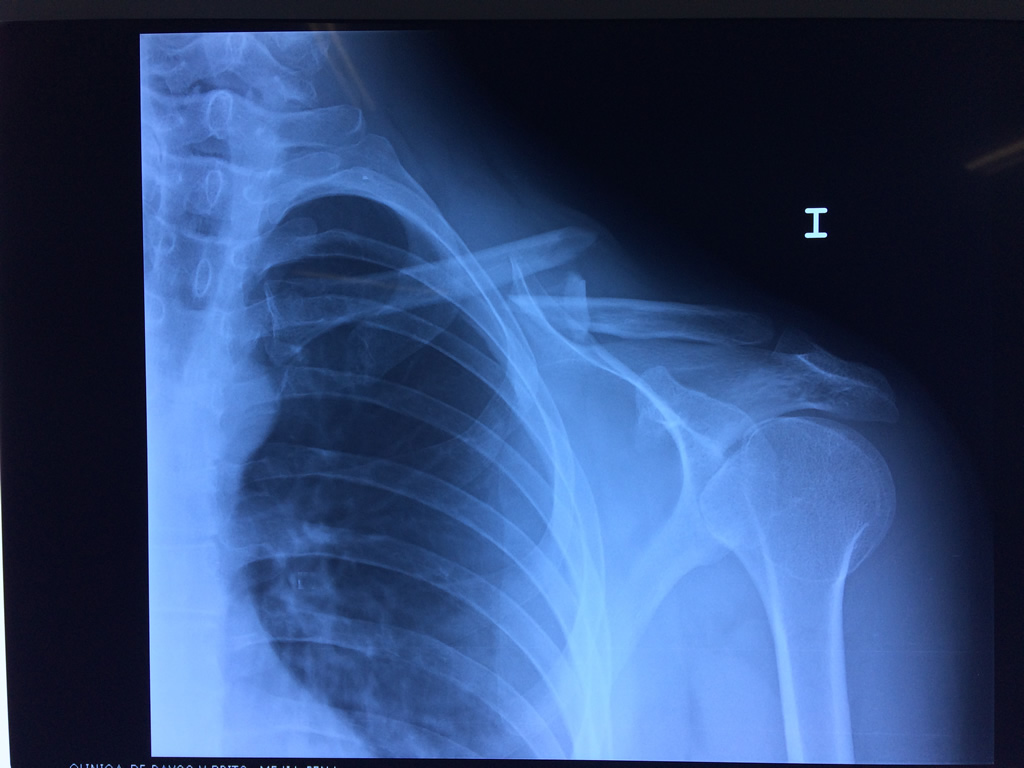

Cirugías de Codos - Clavícula

La clavícula es un hueso largo, con forma de "S" itálica, situado en la parte anterosuperior del tórax. Junto con la escápula forman la cintura escapular. Se puede palpar por toda su longitud y se extiende del esternón al acromion de la escápula, siguiendo una dirección oblicua lateral y posterior.

Se considera el único medio de unión entre el miembro superior y el tórax. A pesar de su aspecto, similar al de un hueso largo, posee una estructura semejante a la de un hueso plano, ya que carece de epífisis y de diáfisis, lo que la harían entrar dentro de la clasificación de hueso largo. Carece de un canal medular propiamente dicho.